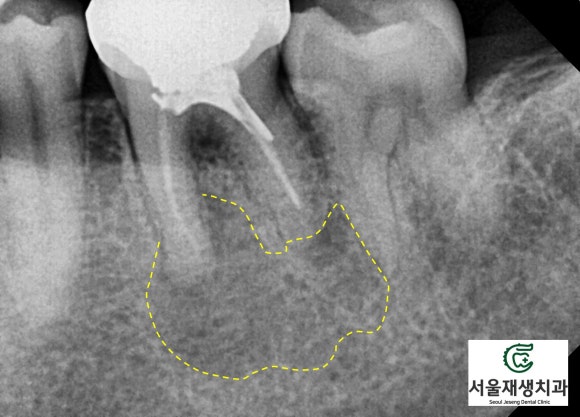

위에 소개된 세 케이스 모두 병소의 크기가 큰 편이었으나,

꾸준한 치료로 모두 새생명을 얻었답니다^^

<병소가 큰 재신경치료 케이스의 비포 애프터>

(6개월 소요)